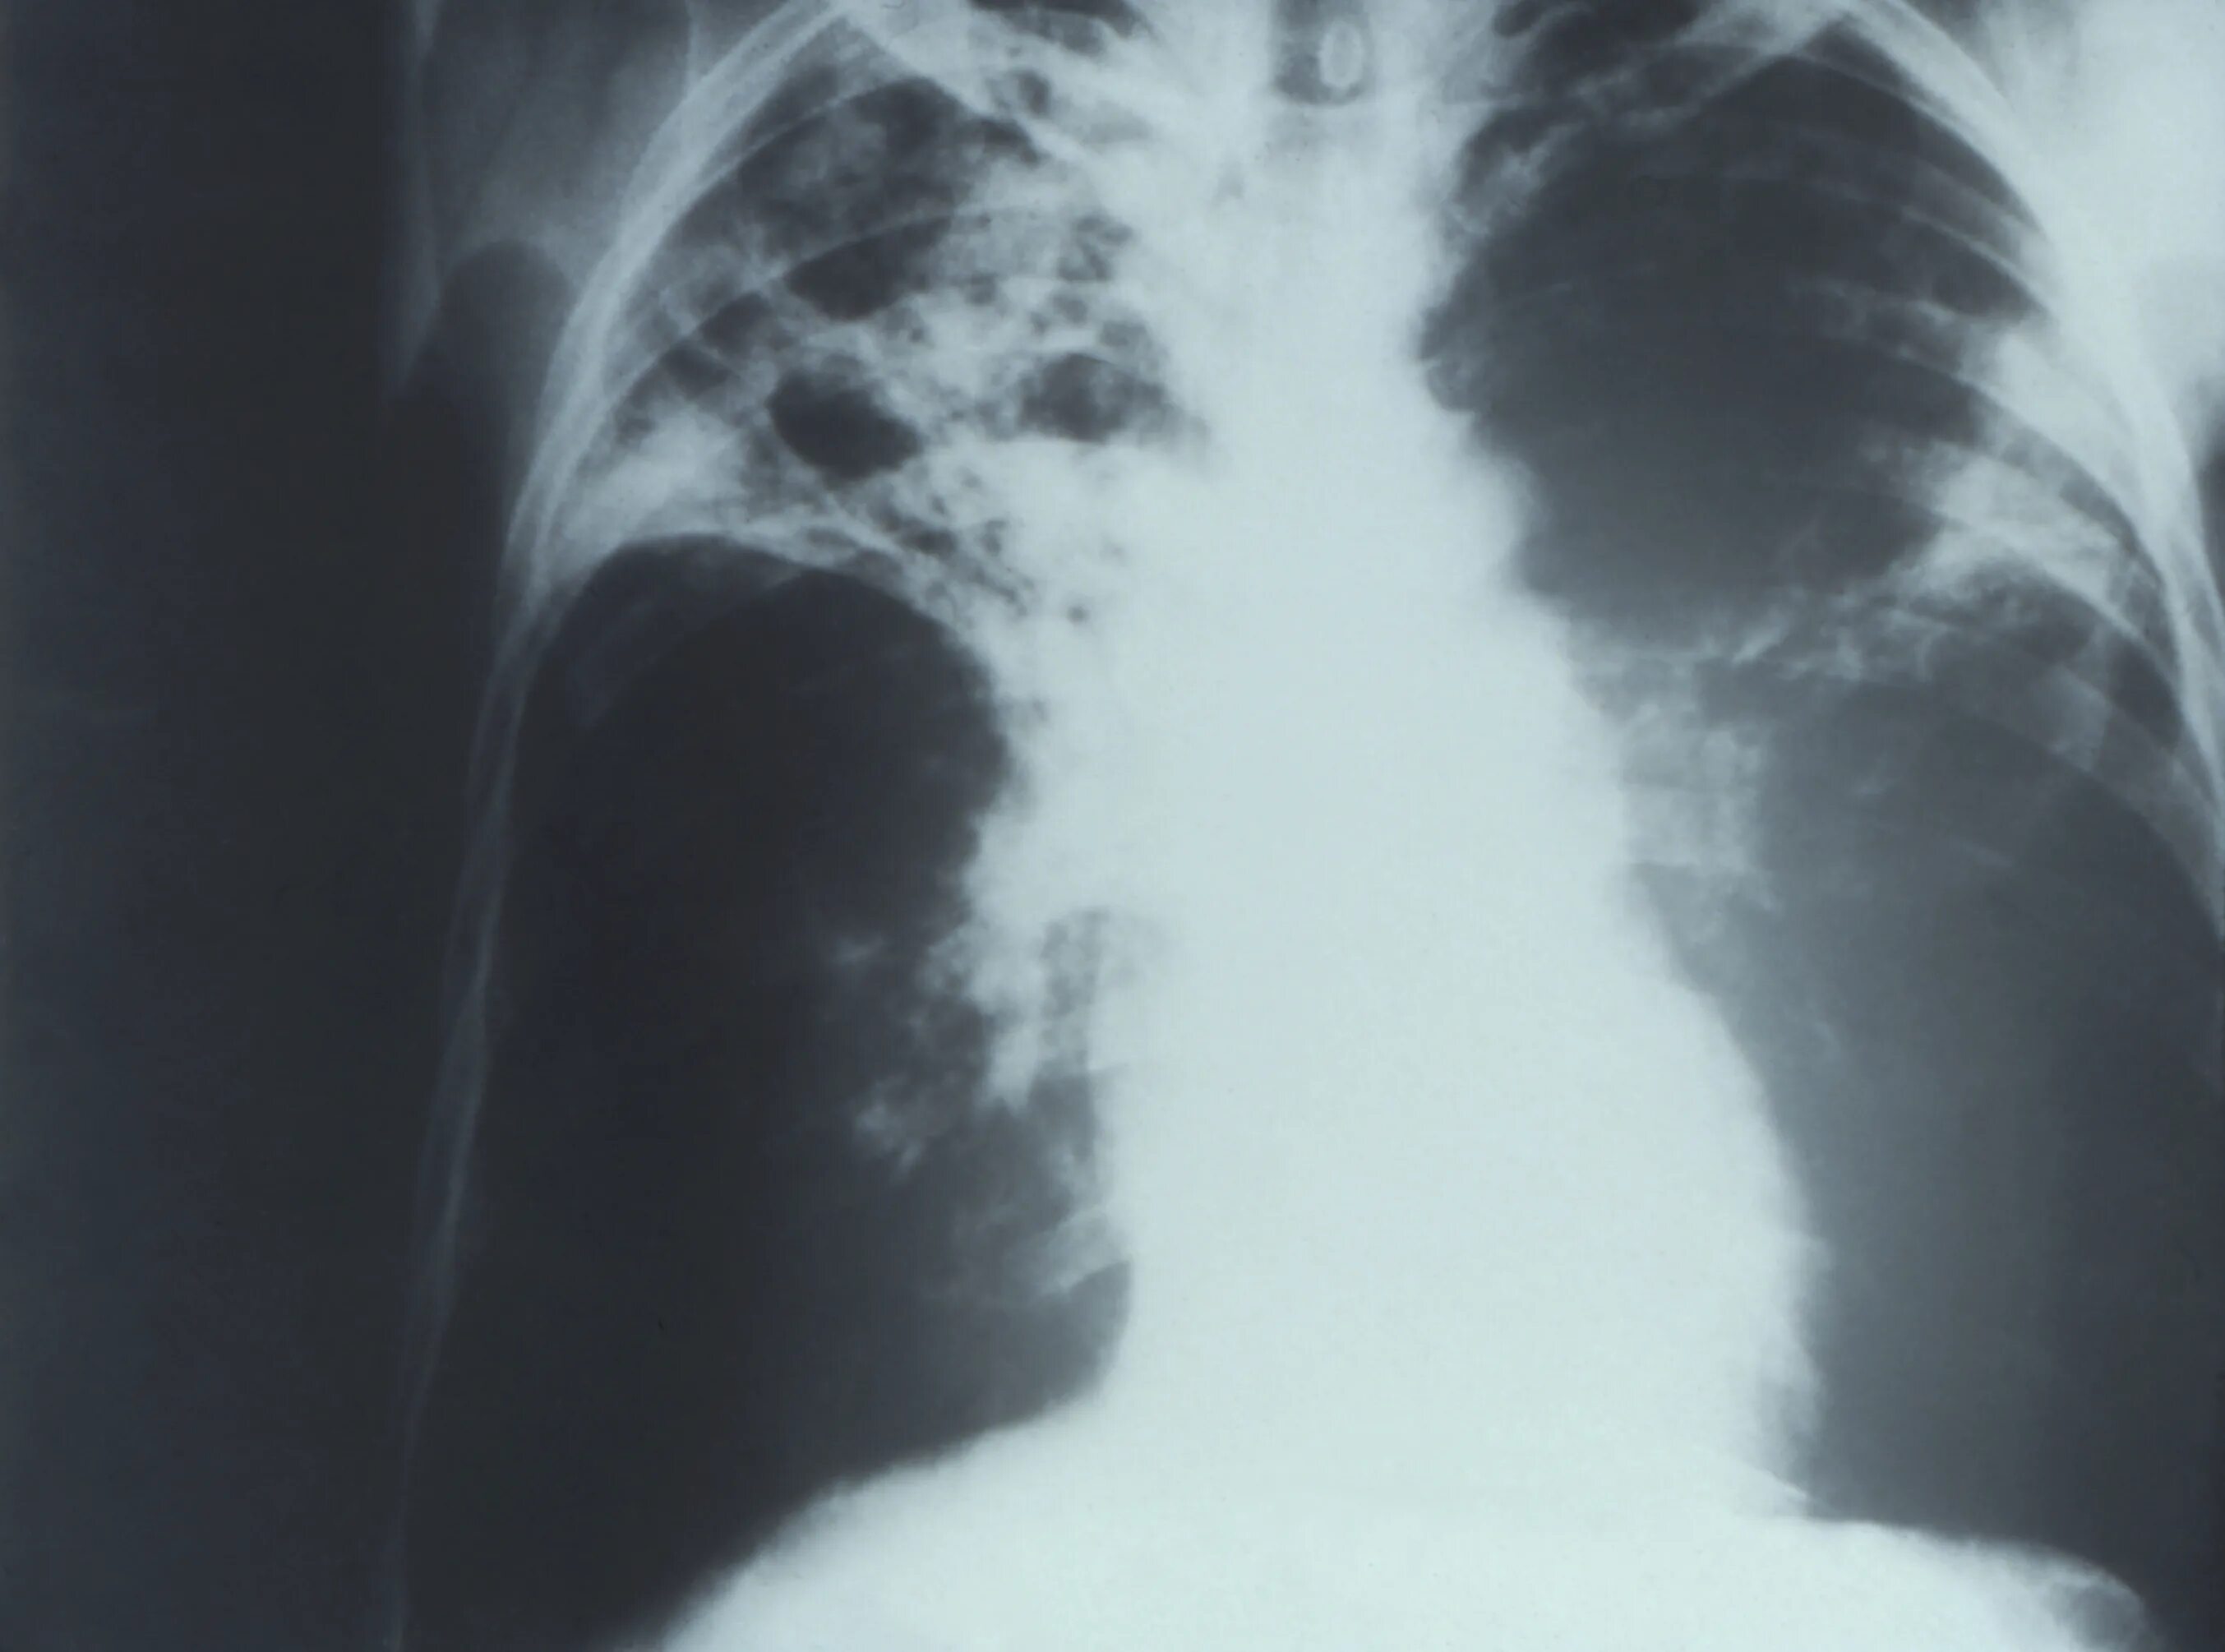

Поражение легких при туберкулезе